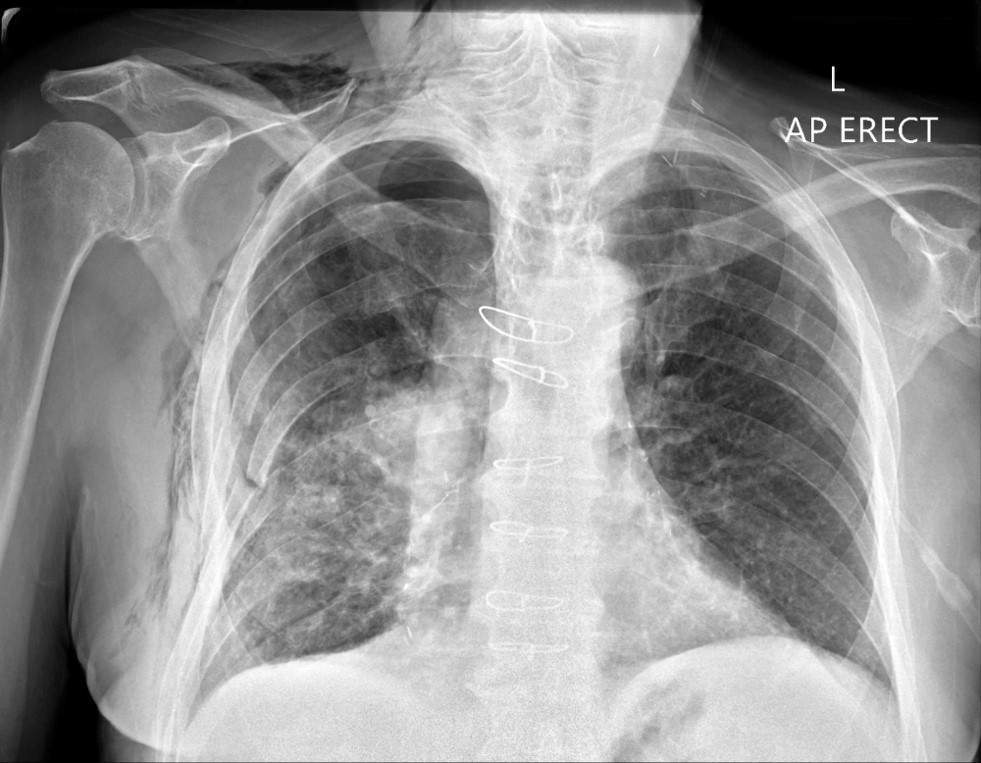

Which of these findings can NOT be clearly identified in this chest x-ray?

a) Rib fractures

b) Surgical emphysema

c) Sternotomy wires

d) Endotracheal tube

e) Right pulmonary contusion

A

What is the most accurate description of this chest x-ray?

a) Left pneumothorax

b) Normal chest x-ray

c) Covid pneumonitis

d) Right lower lobe pneumonia

e) Congestive heart failure